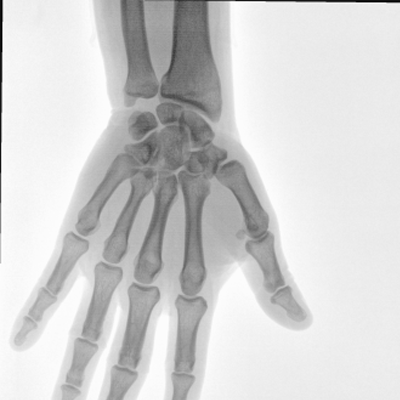

動態(tài)板C形臂 開啟清晰影像新篇章

大尺寸動態(tài)平板探測器,高DQE、低噪聲、圖像清晰。采用多分辨率圖像增強(qiáng)處理技術(shù),不同部位不同圖像處理算法,滿足客戶多樣化的需求。

采用智能變頻脈沖透視技術(shù),優(yōu)化圖像質(zhì)量的同時降低輻射劑量,呵護(hù)醫(yī)患健康